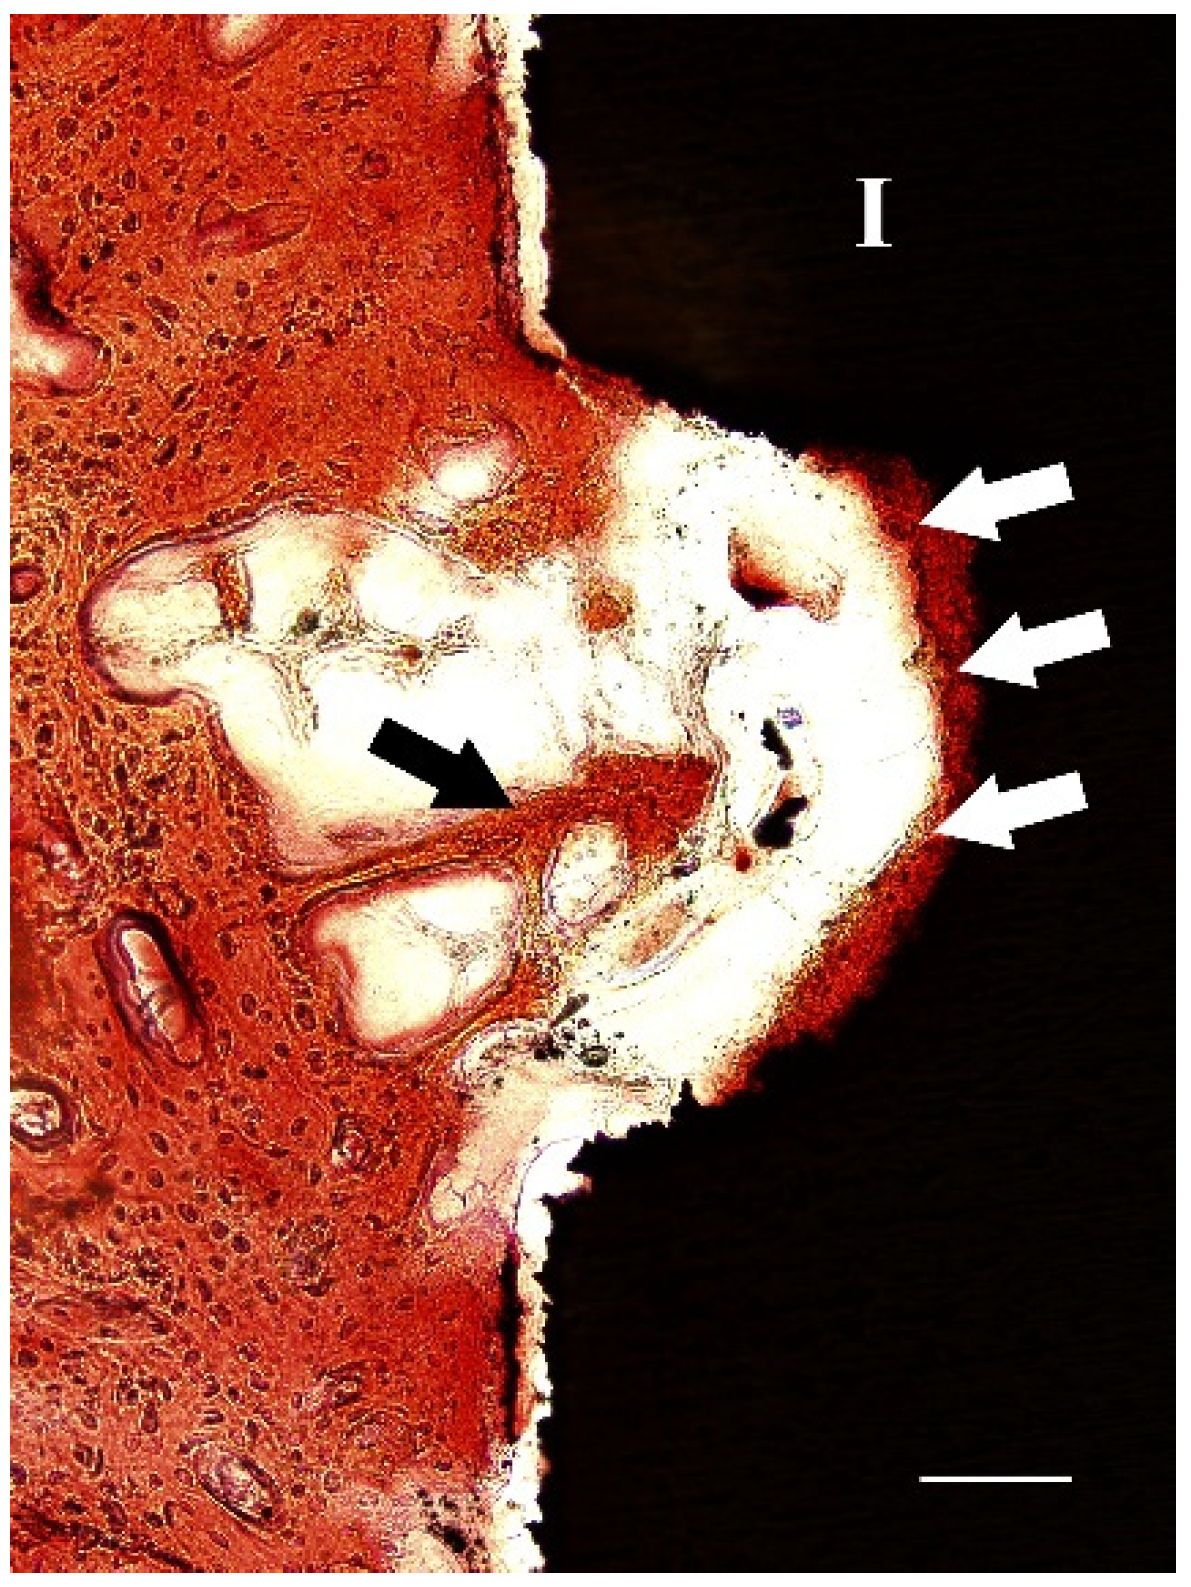

2.3. Histological Study

After two weeks of implantation, histological sections revealed that irregular and disorganized orientations of trabeculae resembling woven bone were formed close to the marrow space and towards the dental implants (Figure 5a). These newly formed trabeculae were more frequently observed after implantation with nacre powder than after implantation without nacre powder. At four weeks after implantation (Figure 5b), woven bone in contact with the implant surface was frequently found in histological sections of dental implants with nacre powder, rather than those without nacre powder. Non-mineralized matrices stained light green-blue were seen in sections of the implantation without nacre powder more than in implantation with nacre powder. It is worth noting that a thin layer of calcified tissue stained with Alizarin red S was found deposited directly on the surface of dental implants with nacre powder. Some bone cells were seen within this tissue (Figure 6). At six weeks after implantation (Figure 5c), it was shown that bone tissue at the site of implantation with nacre powder was in more continuous contact with the dental implant surface than at the site of implantation without nacre powder. Moreover, the circular arrangement of bone cells was more regular between weeks 2 and 4. The results of histochemical staining were consistent with those of micro-CT analyses.

Figure 6.

A light micrograph of a section of XiVE® implant after 4 weeks of implantation with nacre powder, showing an area of mineralized tissue with bone cells (white arrows) attached directly to the implant surface. Trabeculae (black arrow) were found approaching the implant surface; I, implant. Bar = 100 µm. Stevenel’s blue and Alizarin red S stain.

In this present study, histologic ground sections of the implant and surrounding bone tissue were examined using Alizarin red S and Stevenel’s blue staining after two, four and six weeks of implantation. The positive staining of Alizarin red S and Stevenel’s blue were clearly detected as orange-red and green-blue areas, respectively. This result is supported by previous published studies. A thin layer of calcified tissue stained with Alizarin red S found in this study deposited directly on the implant surface of the nacre powder-presenting group but not the control group is similar to that reported by Marco et al. [31]. The authors demonstrated that the sand-blasted surface of titanium dental implants inserted in sheep femur was widely covered by a thin layer of calcified tissue directly on the implant surface, suggesting contact osteogenesis. Interestingly, Puleo and Nanci [32] reported that contact osteogenesis is 30% faster than distance osteogenesis. Contact osteogenesis may better contribute to the development of biological implant fixation as new bone directly forms on the implant surface. In addition, after four weeks of implantation with nacre powder, trabecular bone was found close to the implant surface, suggesting distance osteogenesis. This trabecular bone is particularly suitable for the implant healing process, as it shows a very active wide surface area contiguous with marrow spaces, including many vessels and mesenchymal cells [33].